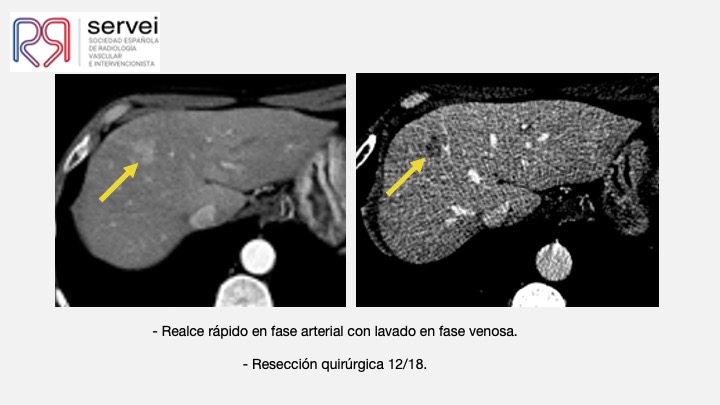

- Ablacion estereoataxia lesiones hepaticas 03